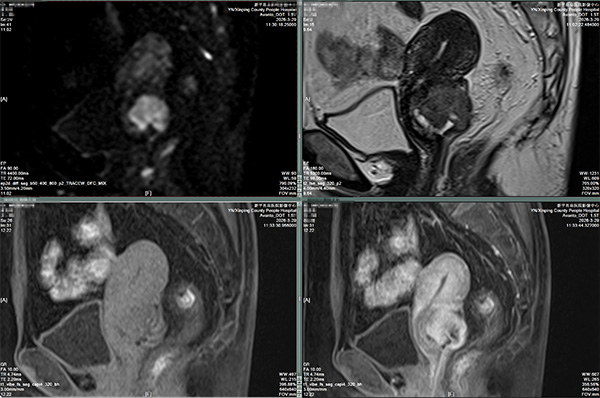

3.诊断超靠谱。结合DWI高信号和ADC值的高低,能精准区分病变良恶性,大大减少误诊漏诊。

图二:DWI快速识别发现肿瘤,可初步判断良恶性倾向。